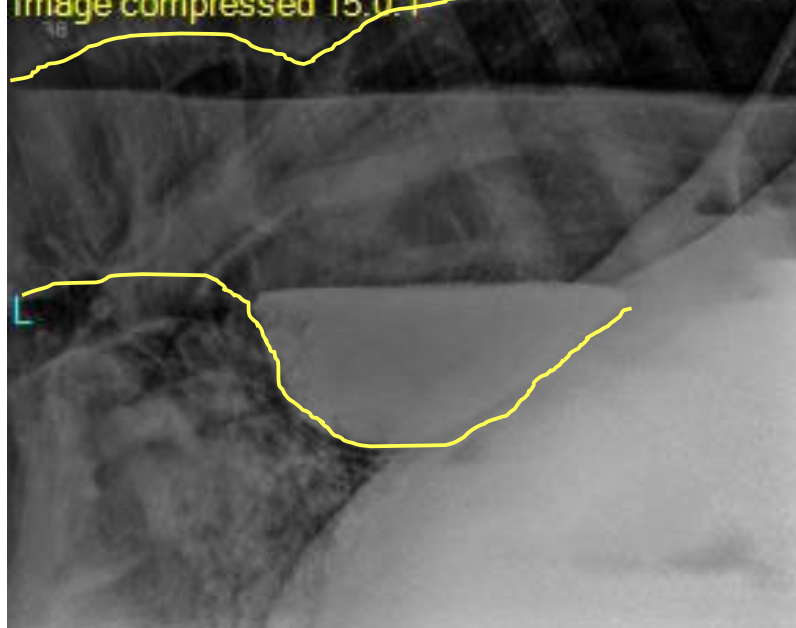

how are radiographs helpful for diagnosing choke in horses?

can help identify:

-location and length of obstruction

-evidence of esophageal rupture

-esophageal abnormalities (diverticulum, megaesophagus, stricture)

-assess lungs

endoscopy, barium swallow studies

barium swallow

definitive diagnosis via endoscopy, esophogram (barium swallow)